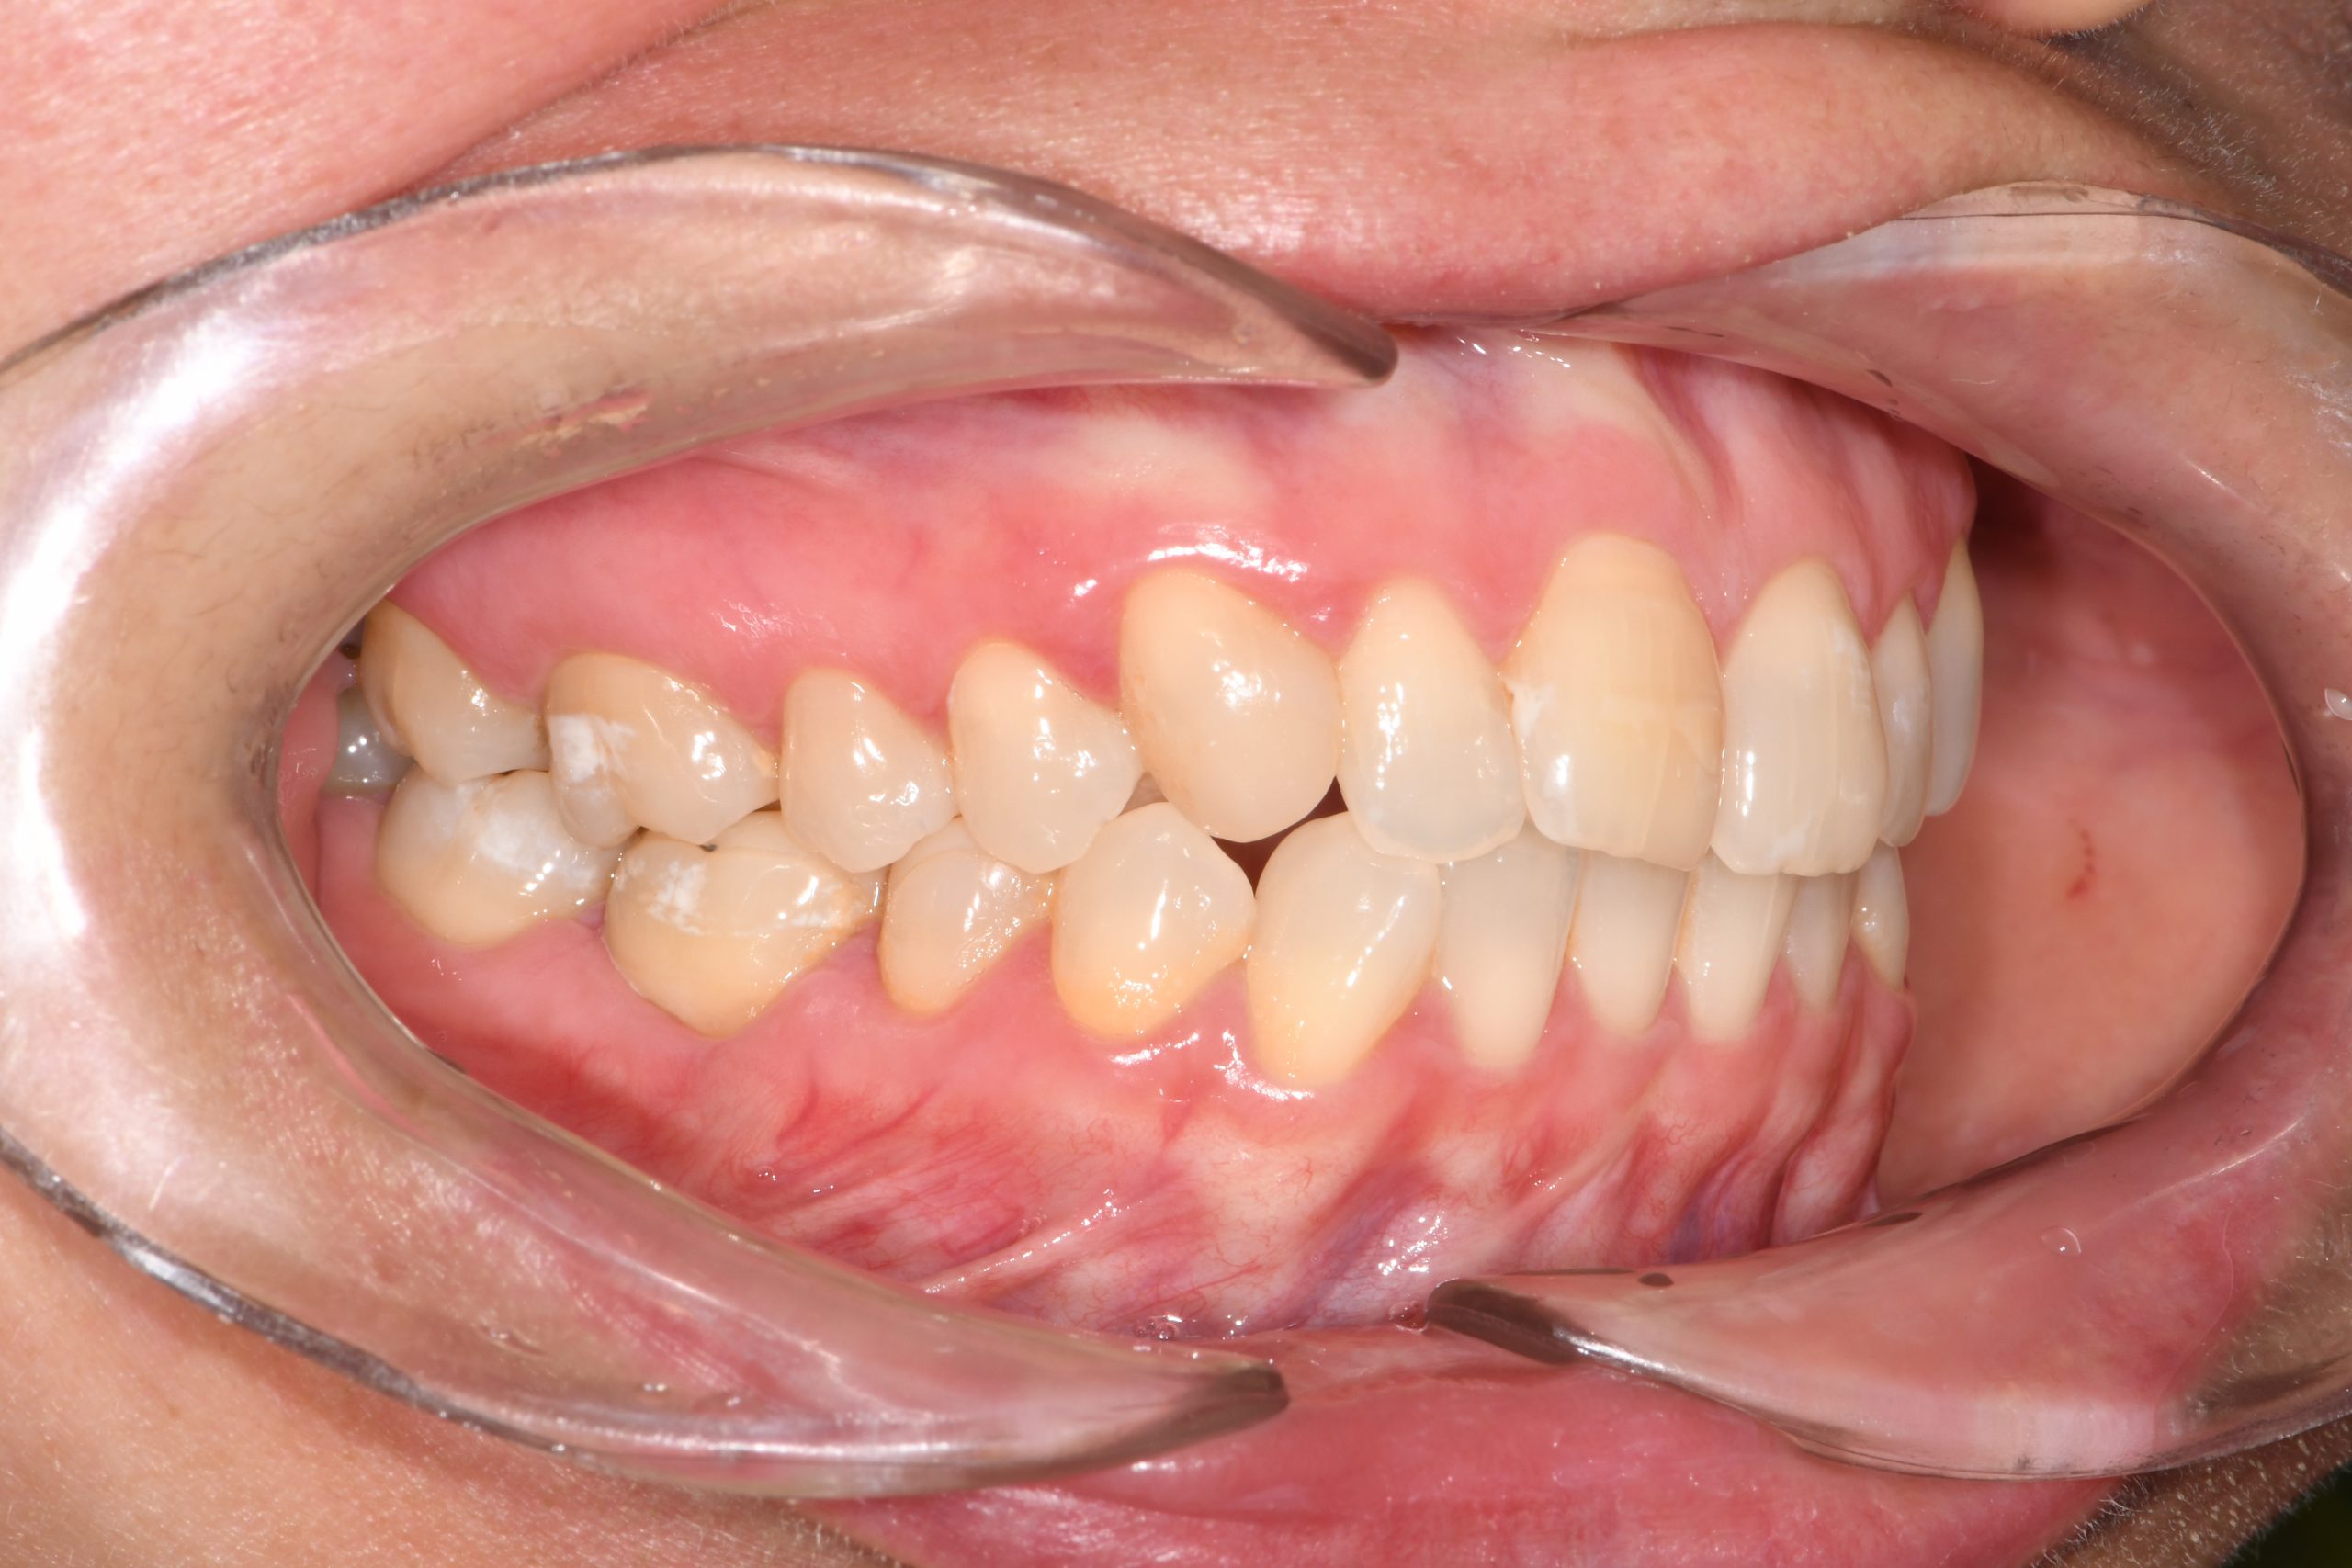

Az elmúlt évekből rengeteg szakmai referenciát tudnánk bemutatni, amelyek különböző fogszabályozási problémákat oldottak meg. Válogatva a több száz esetből, ezen az oldalon olyan képeket, információkat igyekeztünk bemutatni, amelyeknek a segítségével a jövőbeni pácienseinknek azt tudjuk üzenni: A Te fogsorod is lehet gyönyörű!

(Képeket a Pácienseink külön írásos beleegyezésével mutatjuk be!)